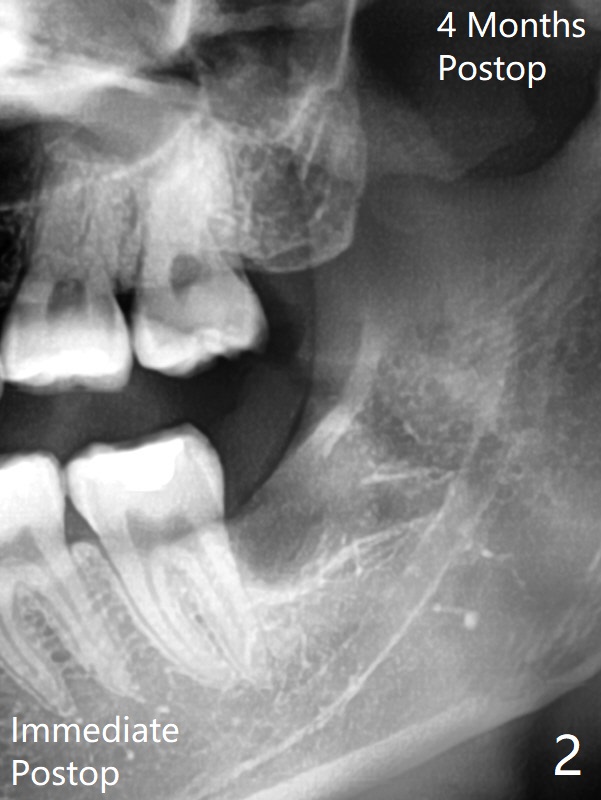

23岁女右上,左上8蛀牙(图一),左上拔除4个月后,回来拔除左下8(图二),为了防止干槽症,放置胶原塞。